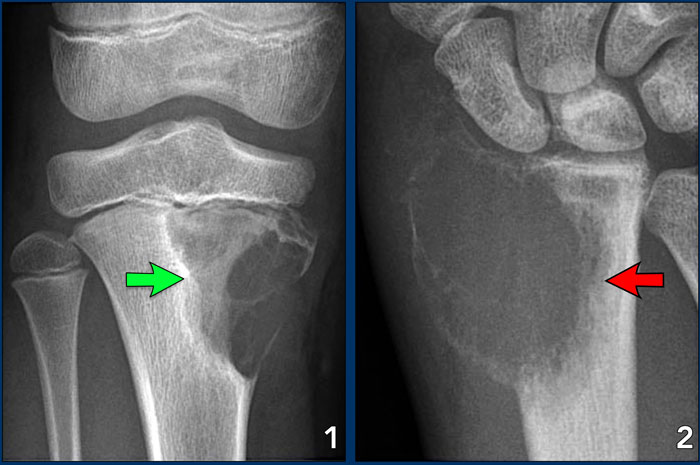

On the left three bone lesions with a narrow zone of transition.

Based on the morphology and the age of the patients, these lesions are benign.

Notice that in all three patients, the growth plates have not yet closed.

Images

1. Non-ossifying fibroma

2. Solitary bone cyst

3. Aneurysmal bone cyst